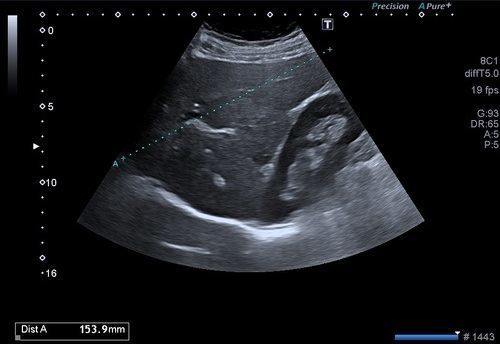

Batın ultrasonogafisi ile karaciğer, böbrekler, böbrek üstü bezleri, pankreas, safra kesesi, mesane, rahim, yumurtalıklar, prostat gibi belli başlı organlar değerlendirilir.

Böbreklerin kist ya da kitleleri, böbrek taşları, böbrek kanallarında genişleme ve tıkanıklık, ciddi böbrek enfeksiyonları (pyelonefrit), böbrek üstü bezlerinin kitleleri ya da kalınlaşmaları, pankreasın enfeksiyonları, kist ya da kitleleri, pankreas kanalı tıkanıklıkları, mesane duvarı kitleleri, divertikülleri, mesane duvar enfeksiyonları(sistit), mesane taşları, rahim duvarından köken alan myomlar, rahimin içerisinden kaynaklanan kitleler, rahim kanalı hastalıkları, yumurtalıkların kist ya da kitleleri, içerisindeki follikül sayıları, endometrioma gibi kanamalı kitleler, prostat büyümesi, kitleleri gibi birçok hastalık batın ultrasonu ile değerlendirilir.